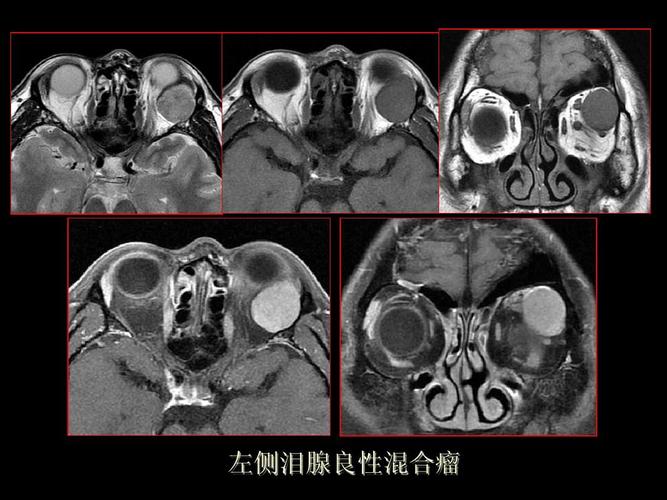

泪腺肿瘤图片

泪腺肿瘤图片,泪腺肿瘤手术术后照片

左眼泪腺多形性腺瘤

泪腺肿瘤

【ppt】泪腺肿瘤及肿瘤样病变的影像学诊断

泪腺混合瘤

泪腺混合瘤的症状图片